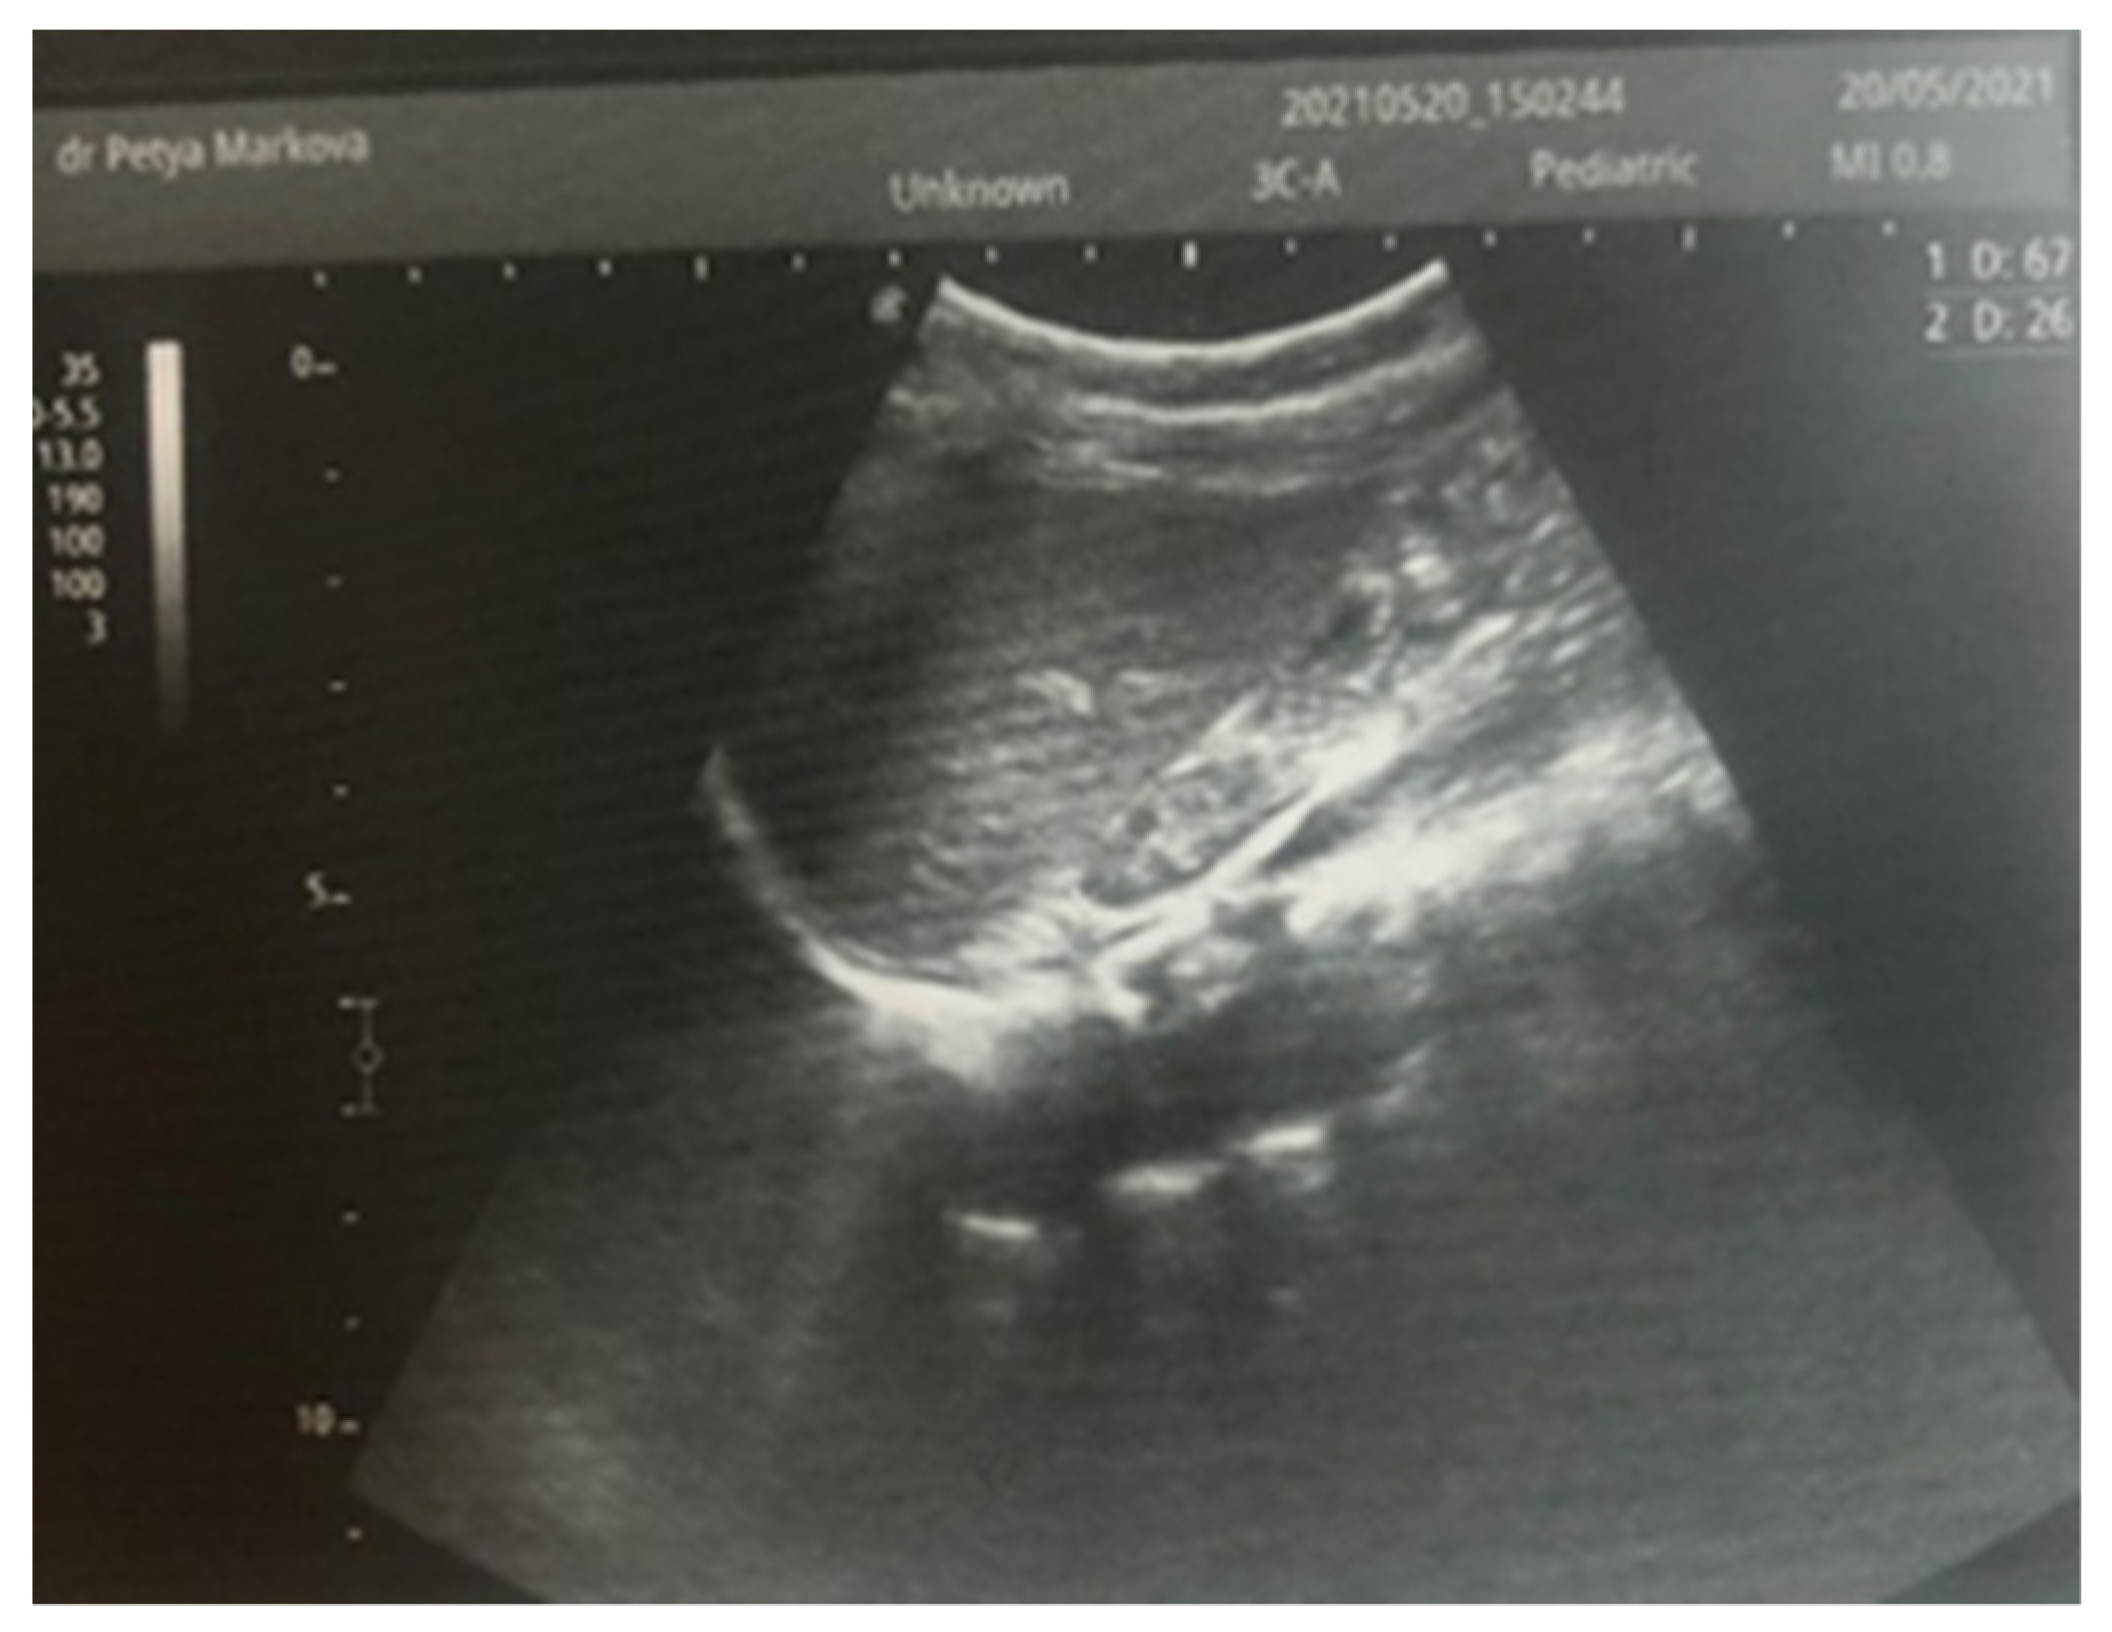

Complex therapy was performed—mechanical ventilation, antibiotics in doses adjusted according to creatinine clearance, anticonvulsants, low-molecular-weight herapin (Enoxaparin), inotropic (Dopamine), and phototherapy. The child’s condition gradually improved and he was extubated on the 9th day of the stay in the NICU. An uncomplicated post-extubation period followed. In the following 2–3 days, macroscopic hematuria was observed. On the second day after extubation, the child’s diuresis was good. The condition of the right kidney was monitored by ultrasound on the 3rd day (Figure 3), the 10th day (recovery of renal venous blood flow was observed), and at the end of the first month. On the 10th day, a decrease in kidney size was noted, and at the end of the first month, the size was below the norm for the age—i.e., the onset of renal atrophy. Follow-up examinations at 6 months and 1 year showed evidence of the atrophying of the right kidney with a longitudinal size of 2 cm, the occurrence of compensatory hypertrophy of the left kidney, normal blood pressure, and preserved renal function (Figure 4).

Figure 3. Right kidney image taken on the third day after birth—increased size, increased echogenicity of the parenchyma, and loss of cortico-medullary differentiation.